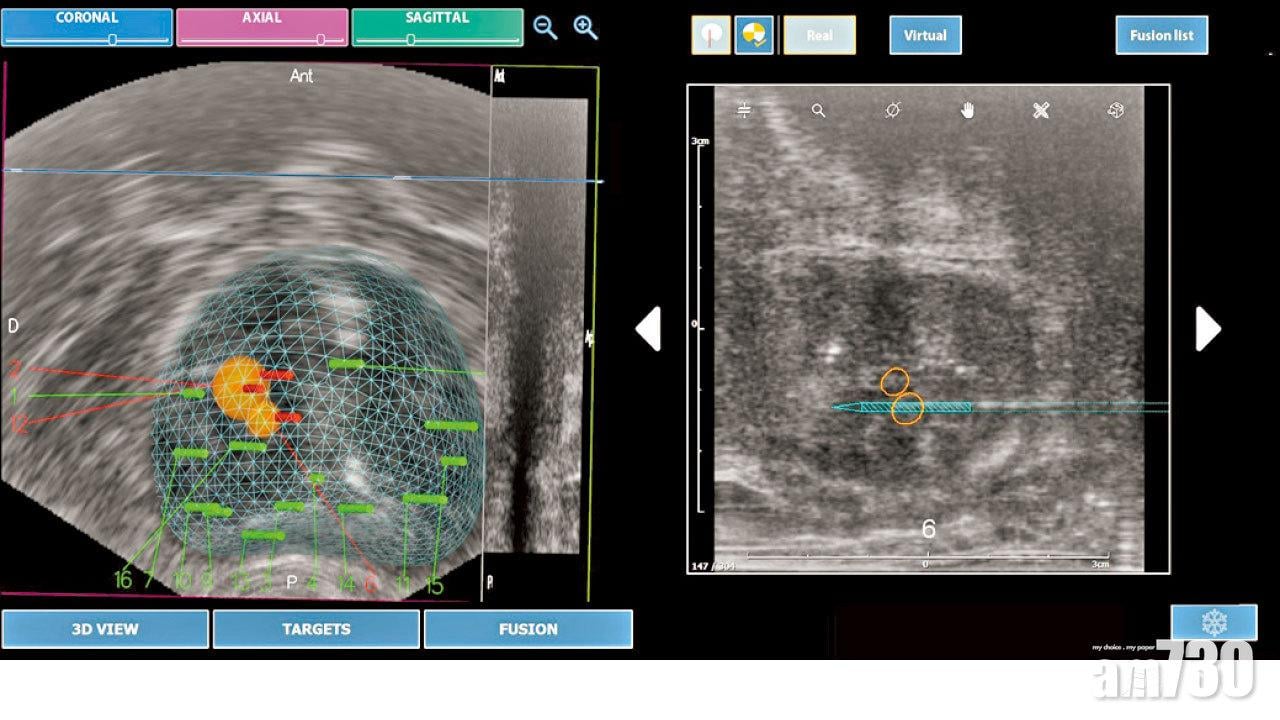

利用融合技術將超波聲和磁力共振影像結合將前列腺腫瘤定位,再配合微波或HI-FU治療,大大提高治療成效。

以前沒有融合技術,醫生主要靠自己的經驗及超聲波的影像引導,估計懷疑有前列腺腫瘤的位置抽針。可是,在抽針觸碰前列腺時,前列腺會隨之變形,影響落針的準確度。特別是當前列腺腫瘤體積較小的時候,抽針過程便有可能出現誤差。後來發展出將MRI及超聲波兩者影像融合技術,讓醫生更準確知道前列腺腫瘤的位置,不但增加抽針的準確度,更提高之後手術治療的成功率,增加病人存活機會。